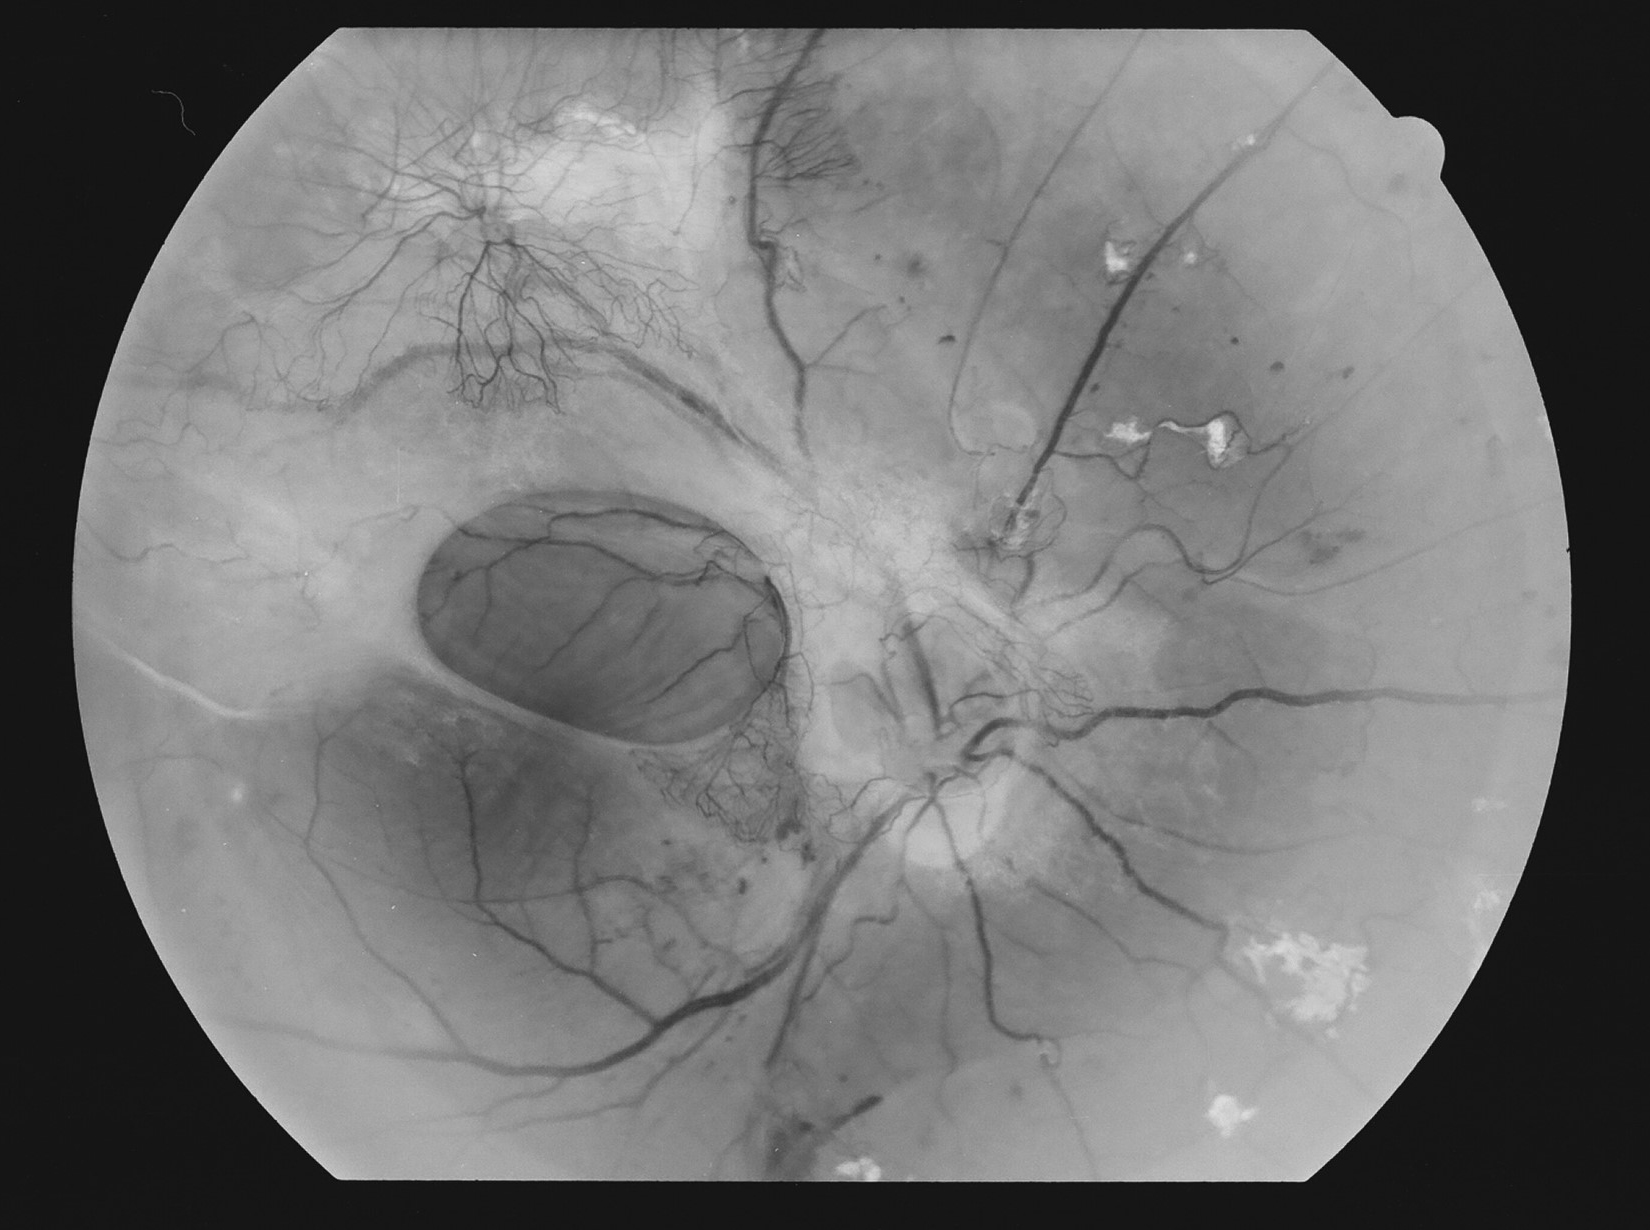

Kuva 8.

Diabetes, proliferatiivinen retinopatia, oikea silmä. Mikroaneurysmia, mikroinfarkti, IRMA:a ja uudissuonikasvua temporaalisesti.

Kuva 9.

Diabetes, proliferatiivinen retinopatia, vasen silmä. Mikroaneurysmia, vuotoja, IRMA:a ja pieni uudissuoni.